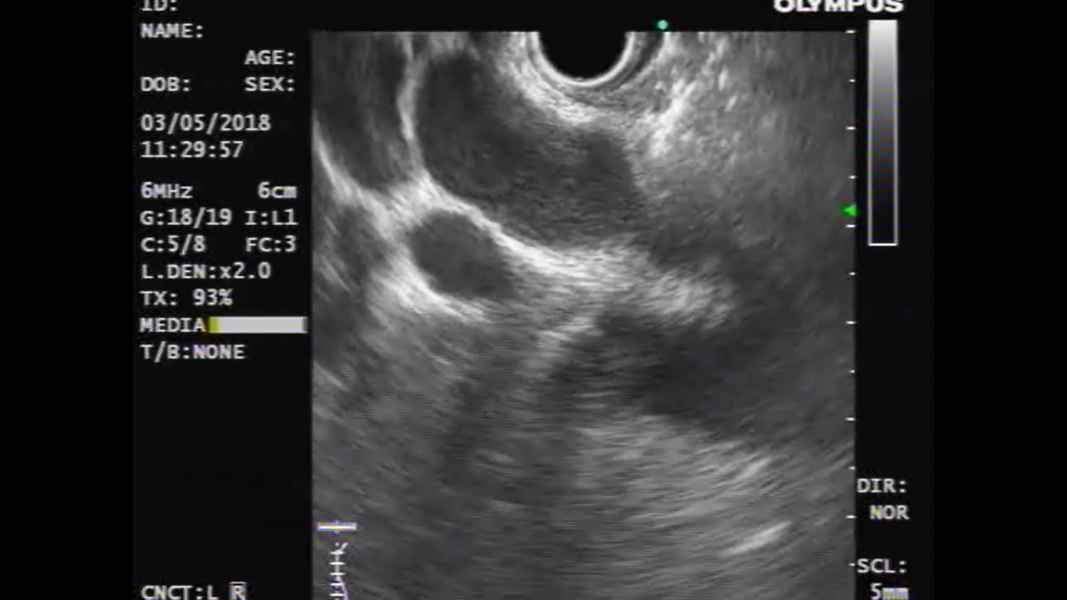

Palliative ultrasound-guided choledochoduodenostomy using a lumen-apposing metal stent

Vídeo